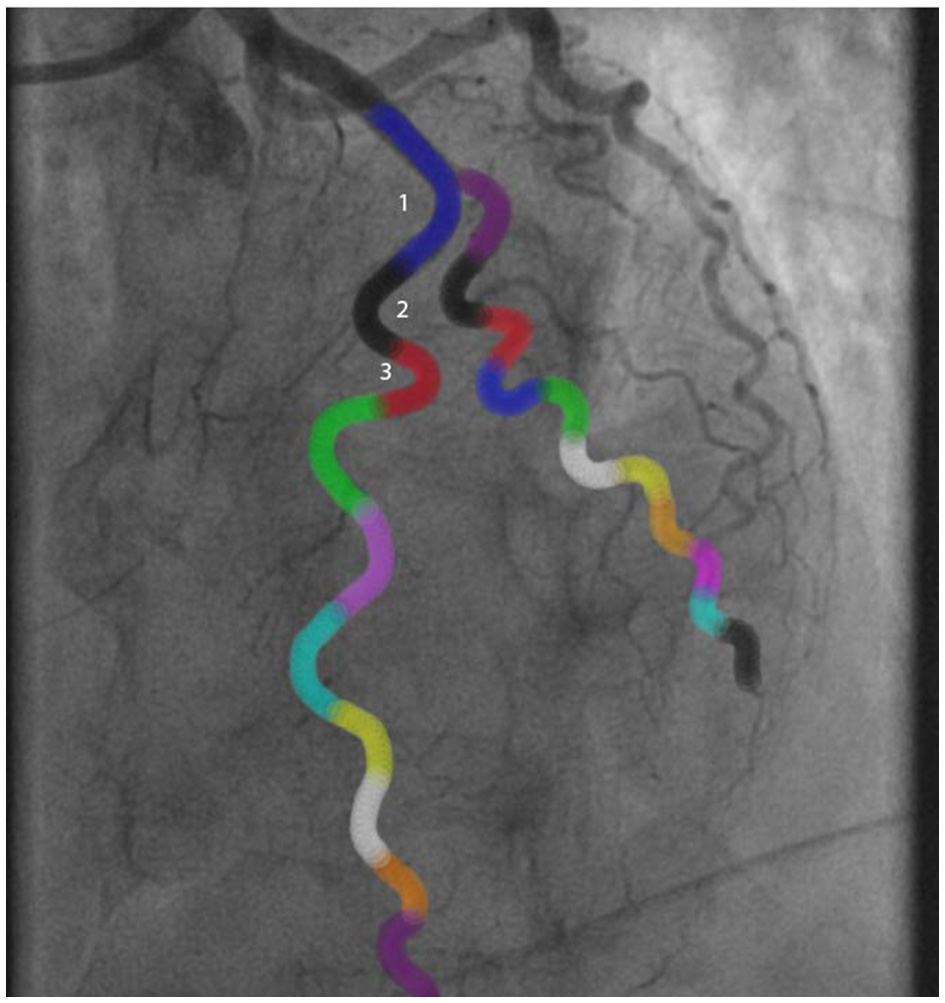

Figure 2

Example of a tortuosity assessment of the left anterior descending artery. The angles of all colored curvatures were measured to assess tortuosity: 1Blue curvature = 100°, 2Black curvature = 125°, 3Red curvature = 150°. In this case there was moderate tortuosity.